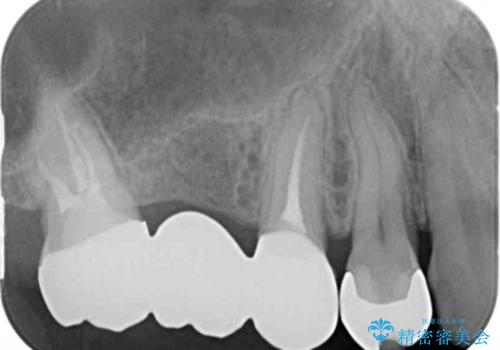

- 上顎臼歯部の欠損にブリッジ治療、目立つ下顎奥歯の銀歯をセラミックへの置き換えを希望され来院されました。

審美性と耐久性に優れるフルジルコニアクラウンでの治療を計画します。